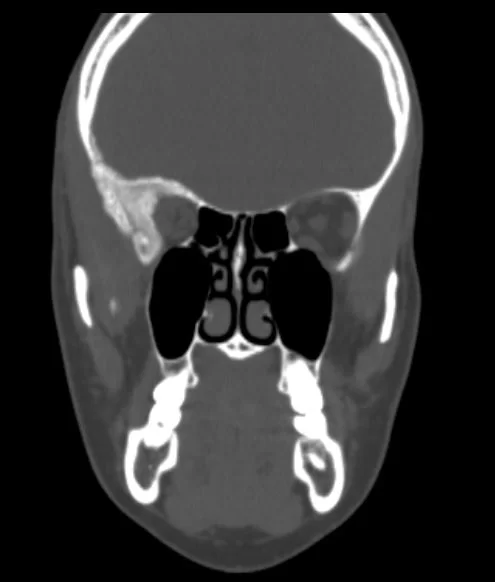

H Μαγνητική  & Αξονική Τομογραφία εγκεφάλου ανέδειξε χωροκατακτητική εξεργασία στην περιοχή της πτέρυγας του σφηνοειδούς οστού, δηλ. του άνω (οροφή) και του πλαγίου τοιχώματος του οφθαλμικού κόγχου. Η εξεργασία επεκτείνονταν κατά μήκος της σκληράς μήνιγγας ενώ στην περιοχή του κροταφικού πόλου παρουσίασε ενδοκρανιακή επέκταση. Η πάχυνση του οστού του κόγχου προκαλούσε πίεση των περιεχομένων του κόγχου με αποτέλεσμα εξόφθαλμο.

Η ασθενής υπεβλήθη σε δεξιά πτεριονική κρανιοτομία, αποσυμπίεση του κόγχου – αφαίρεση του μαλακού τμήματος του όγκου και ανακατασκευή του κόγχου με μόσχευμα πολυαιθυλενίου (Porex)